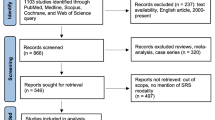

Doses were measured for 20 patients undergoing SRS on a GKP at distances of 18, 43 and 75 cm from the target, corresponding to the approximate positions of the thyroid, breast and gonads respectively. A literature review was conducted to collect comparative data from other radiosurgery platforms. All data was used to calculate the dose to body organs. The National Cancer Institute (NCI) RadRAT calculator was used to estimate excess lifetime cancer risk from this exposure. Five different age groups covering childhood and younger adults were modelled for both sexes.

To compare the extracranial doses from SRS with other stereotactic platforms, a literature review was conducted on PubMed. Publications since 1995 investigating radiosurgery extracranial doses were analysed. Extracranial doses from platforms were plotted as a percentage of prescription dose versus distance from the isocentre, thus eliminating potential bias from different prescription doses between the groups. Where data was recorded as dose to organ, the position of the organ within an average adult was used to convert the measurement point to a distance. Distances within 1 cm were amalgamated. Interpolation was used for comparison where necessary.

A total of four papers were identified as the most comprehensive reports of extracranial doses from modern radiosurgery platforms [9, 13, 18, 29]. Results are recorded in Table 2.